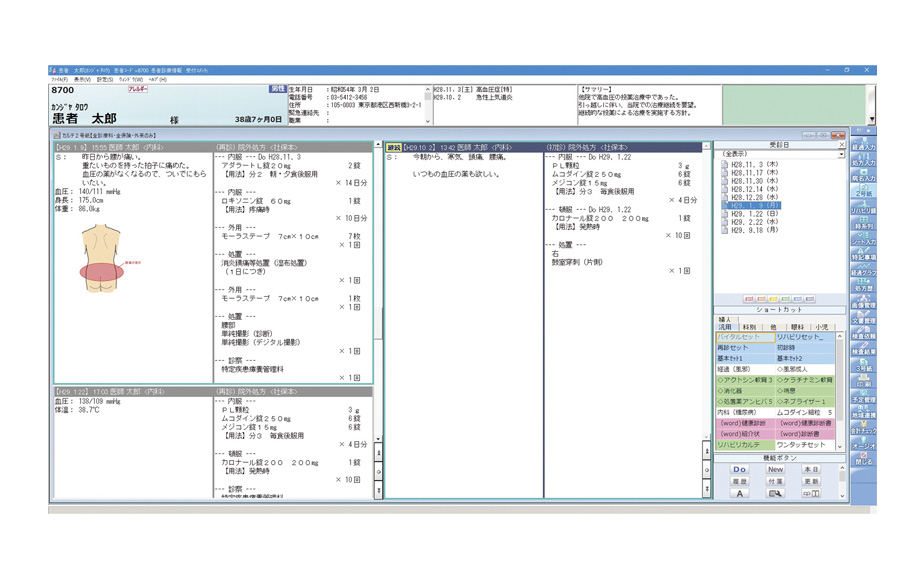

見やすい画面で直感的に操作、電子カルテをスマートに使いこなせます。

ワンタッチセット入力

ワンタッチボタンを指でタップするだけで、よく使う所見や処方などをかんたんに入力できます。

ワンタッチボタンは自由に設定できるので、診療内容を入力する際に必要なものを任意に登録できます。入力は指だけではなく、ペンタッチでもマウスクリックでも可能です。

多彩な機能が記録を残す・患者さんに説明するシーンをスマートにサポートします。